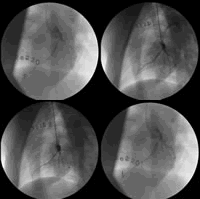

图1 对照组两次诱发冠脉痉挛前后造影图(相关内容见8月31日第20版)

注:图1a 为对照组第一次诱发冠脉痉挛前造影,前降支、回旋支 10 %~30 % 狭窄;图1b 为对照组诱发冠脉痉挛后造影,5-羟色胺诱发冠脉痉挛阳性;图1c 为对照组第二次(1个月后)诱发冠脉痉挛前造影,前降支、回旋支轻度狭窄;图1d 为对照组第二次(1个月后)诱发冠脉痉挛后造影,5-羟色胺诱发冠脉痉挛两支血管均阳性。, 百拇医药